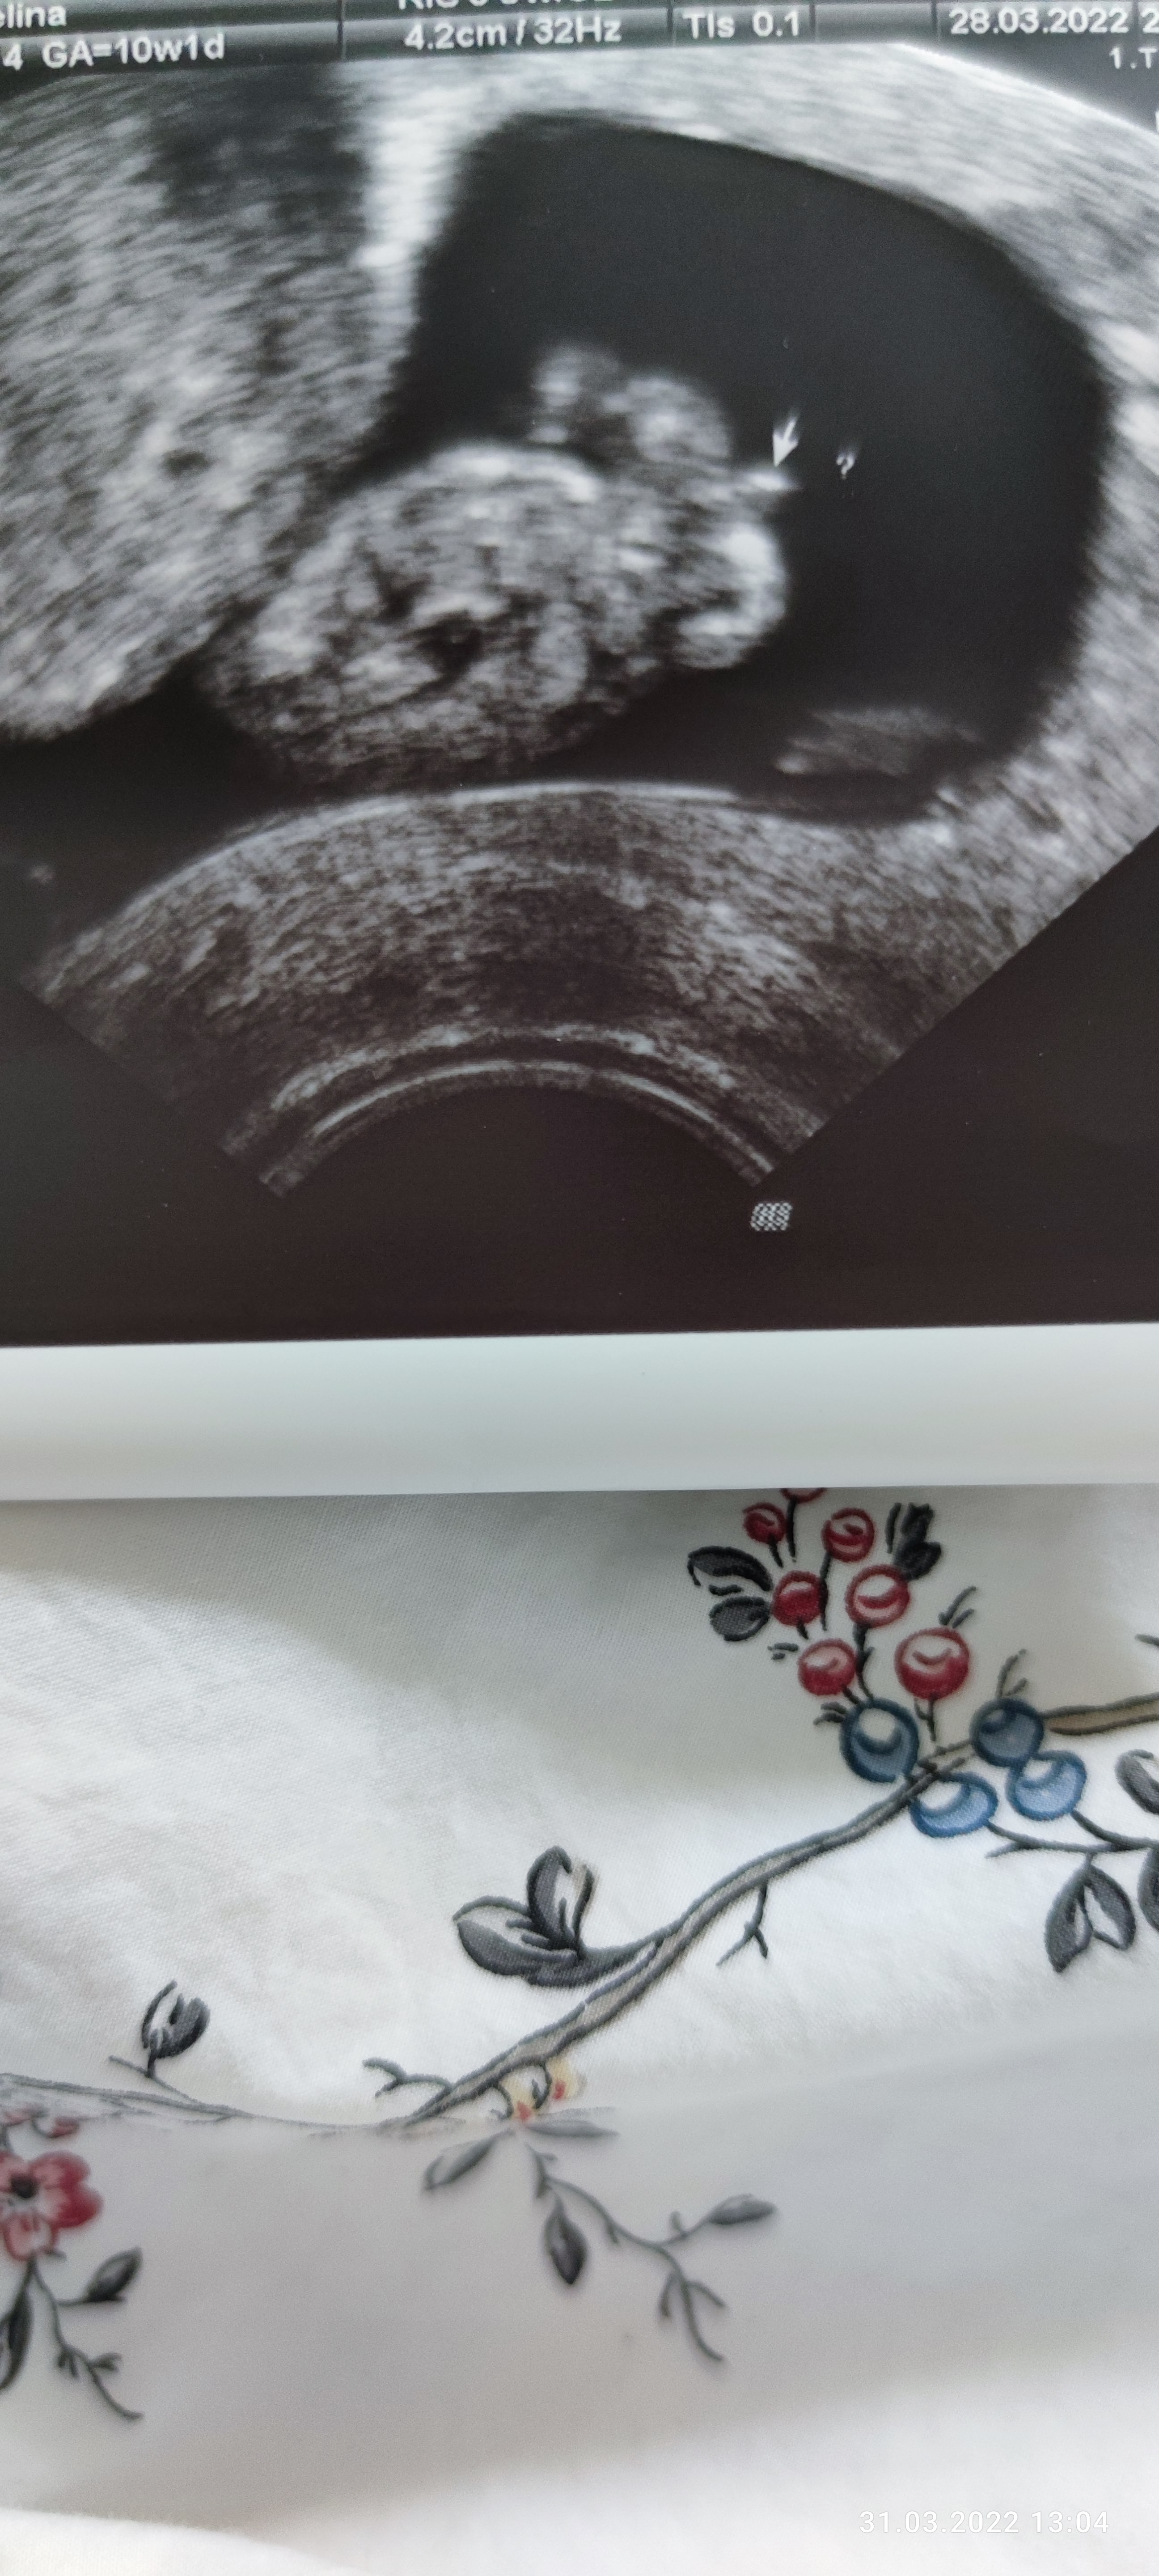

Zdjecie z 10 tygodnia wg. Miesiaczki, z usg 11 tydzien.

Lekarz twierdzi, ze chlopak( powiedzial, ze przypuszcza). Mi tez sie tak wydaje. A jakie jest Wasze zdanie? Czy takowe narzady moga moze jednak nalezec do pannicy?